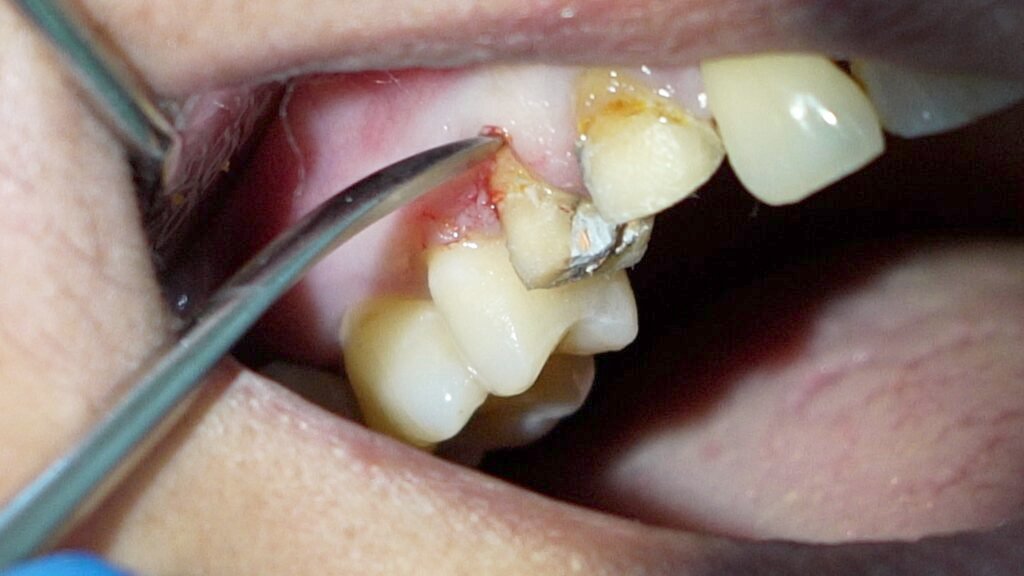

I explained the situation to the patient, noting that the tooth had been treated improperly and both the tooth and broken file would need to be removed. After removing the porcelain crown, I found that the restoration underneath was temporary and that dental caries were not properly cleaned out—an important first step before any root canal treatment